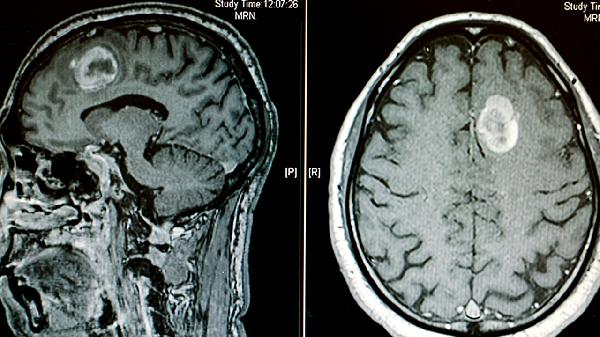

脑肿瘤手术治疗方法主要有开颅肿瘤切除术、神经内镜手术、立体定向活检术、激光间质热疗和脑室腹腔分流术等。具体手术方式需根据肿瘤位置、大小和病理类型决定。

立体定向活检术用于深部或功能区肿瘤的病理诊断。通过影像引导精确定位,用穿刺针获取少量组织进行化验。该技术对淋巴瘤、生殖细胞瘤等需明确性质的病变尤为重要,术后可能出现局部出血或感染。